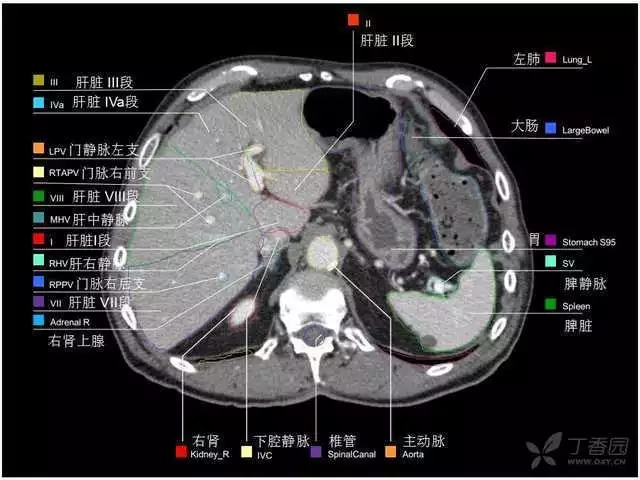

腹部肝脏高清CT断层的图谱

全腹部高清CT图谱,淋巴结彩色图谱,血管解剖图谱大汇总!

肝段,肝内管道的分布规律